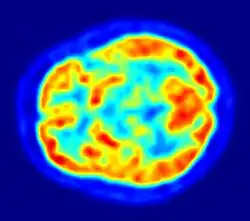

Een hersenscan kan een indicatie opleveren van: alzheimer, hersenbloeding, hersentumor, of parkinson. Hierbij wijzen zwarte vlekken op een gebrekkige doorbloeding (hersenbloeding, alzheimer). Rode gebieden zijn ofwel een indicatie van gezonde fysiologie, ofwel een indicatie van hyperactiviteit en van de grootte en de locatie van een tumor. In de foto hierboven is mogelijks een kleine afwijking in de doorbloeding rechts-pariëtaal.